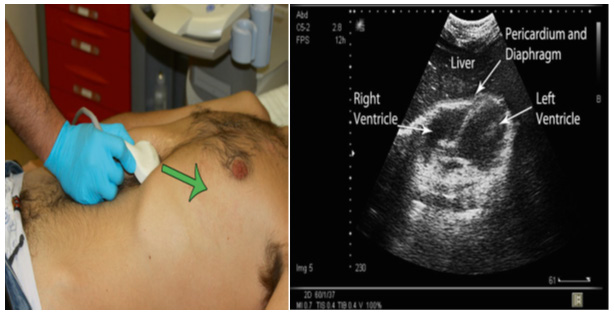

Subxiphoid or subcostal position

The transducer is located below the xiphoid process, almost parallel to the abdominal wall to observe the content of the mediastinum through the left hepatic lobe. The transducer needs to be angled slightly to the patient's left. In this position, the fluid in the pericardial sac around the heart can be clearly seen as a hypoechoic ring (Figure 7).

Figure 7 Subxiphoid window: sectoral transducer, in the lower portion of the xiphoid process, directing towards the patient’s left shoulder.

The effect of fluid on the right ventricle can be seen, although temporal resolution is slow, unless an echocardiographic transducer is used, signs of ventricular compromise can confirm a clinical diagnosis of cardiac tamponade (Figure 7A).

Figure 7A Anechoic image (*) that occupies the pericardium is evidenced, in a patient with closed chest trauma.

More recently, ultrasound has also been shown to be useful in diagnosing pericardial effusions in trauma patients.

The main reason for diagnosing pericardial effusions is to prevent trauma-induced patients from developing pericardial tamponade.

We incorporate the subcostal view of the heart as a part of the rapid examination in all patients with blunt abdominal trauma. This is useful in diagnosing pericardial effusions (Figure 7A).